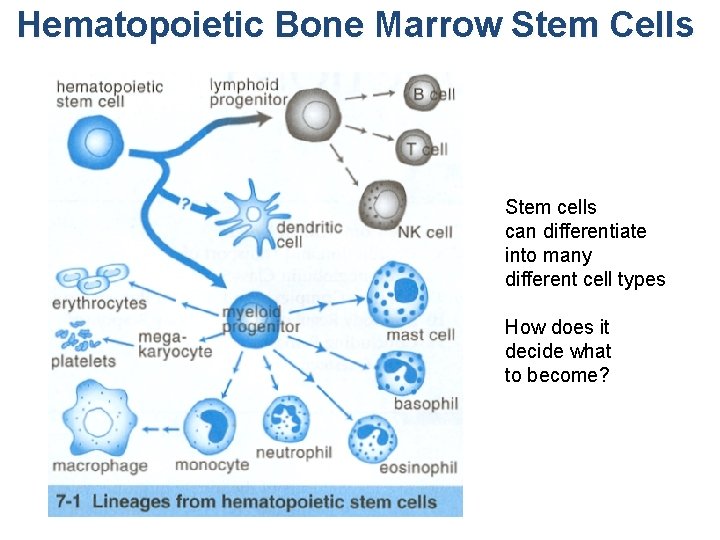

Immunocompetent cells: 1. T-lymphocytes {T-helper, T-suppressor, T-cytotoxic (killer cells), T-memory cells} 2. Natural killer cells(NK-cells) 3. B-lymphocytes 4. Plasma cells 5. Macrophages 6. Granulocytes of the blood(Neutrophilic, Eosinophilic, Basophilic Leucocytes) 7. Monocytes 8. Mesenhymal reticular cells 9. Epithelial reticular cells 10. Antigen Presenting Cells (APC) {Dendritic cells, Langerhans’ cells of the skin, Kupffer’s cells of the Liver, Dust cells of the Lung etc. )

Hematopoietic Bone Marrow Stem Cells Stem cells can differentiate into many different cell types How does it decide what to become?